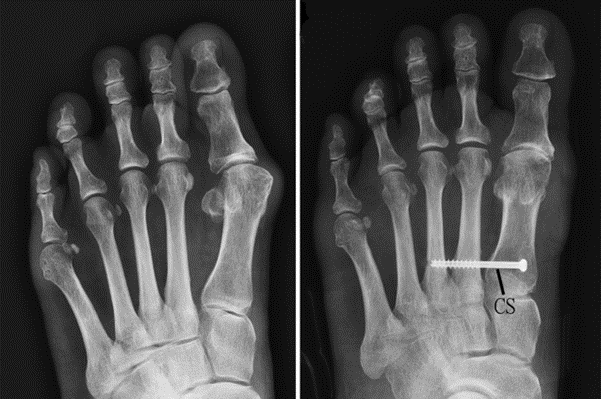

关节镜拇外翻微创矫形术

左图为拇外翻术前X片,右图为矫形术后X光片。